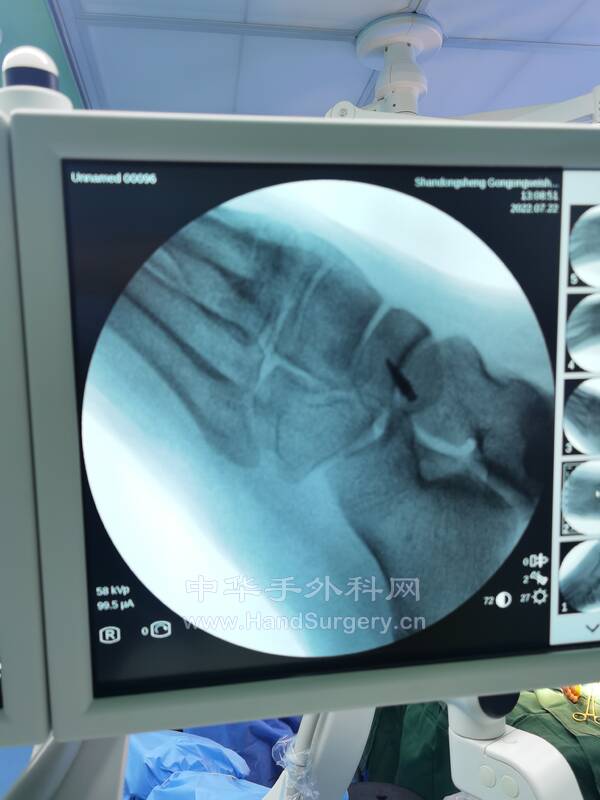

1.副舟骨损伤(图2-6),胫后肌腱止点重建术,手术要点:

选择足背内侧舟骨突起处纵行小切口,长约3cm,显露至骨膜,找到副舟骨,将其完整切除,舟骨内侧缘用咬骨钳咬除关节面,至接近正常舟骨形状,选直径3.5mm的铆钉垂直于骨面拧入,在铆钉两侧用直径1.2mm的克氏针平行贯穿打孔,用圆针缝入2-0(或3-0)可吸收线,连同铆钉缝线编织缝合胫后肌腱止点,闭合切口,术后石膏固定。